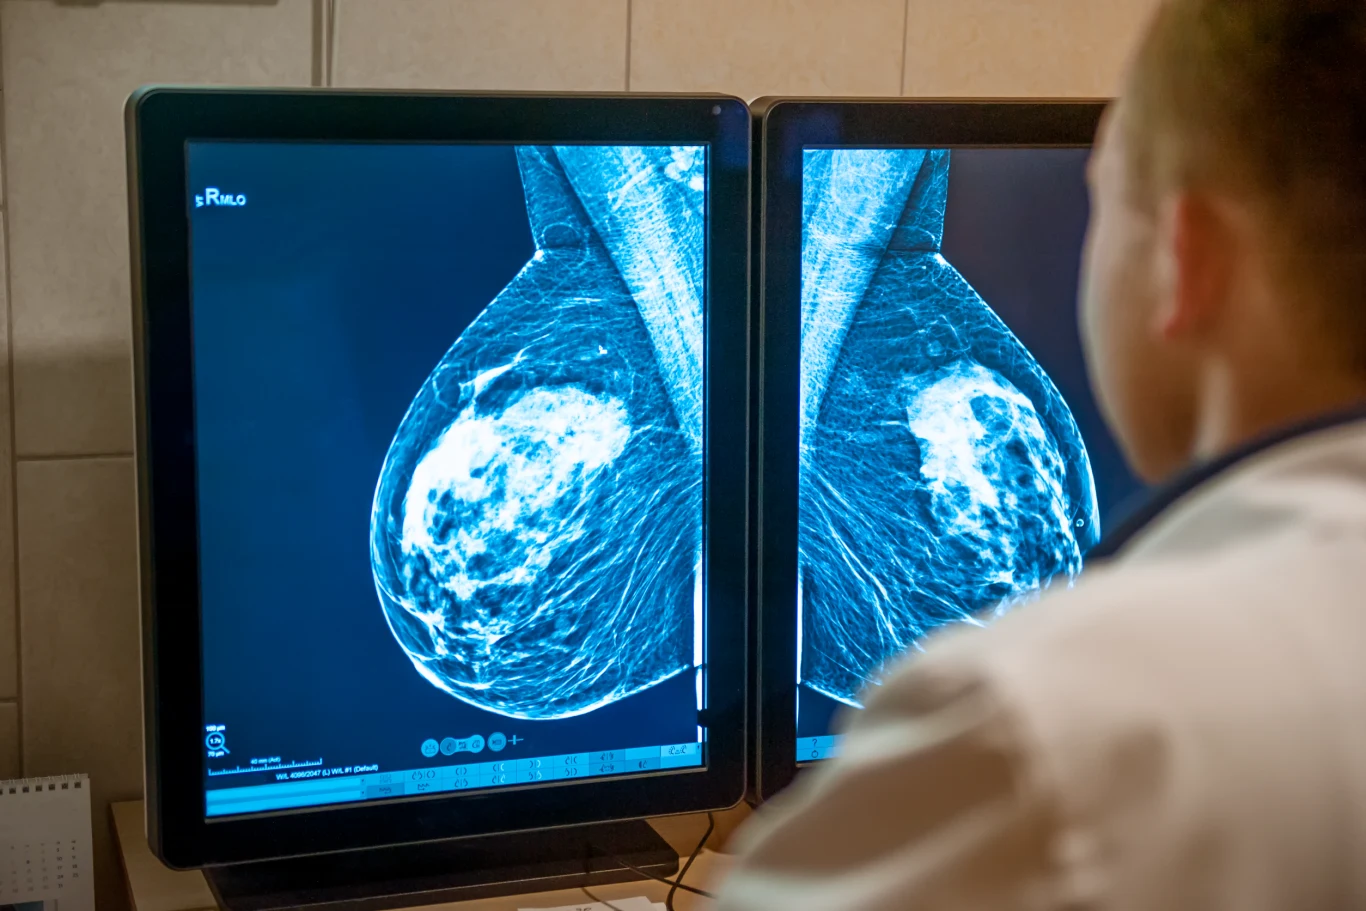

Mammografia szansą na dłuższe życie

Uczestnictwo w badaniach przesiewowych wykrywających raka piesi, które wprowadziła już większość rozwiniętych krajów, w tym Polska, powinno sięgać minimum 70 proc. docelowej populacji. Tymczasem w naszym kraju frekwencja wynosi jedynie niecałe 40 proc. W ostatnich latach (również ze względu na pandemię COVID-19) statystyki są jeszcze gorsze. Specjaliści są jednogłośni - uważają, że dzięki badaniom, u kobiet diagnozowano by zdecydowanie mniej raków zaawansowanych.

Bezpłatna mammografia dla kobiet

Każda kobieta między 50. A 69 rokiem życia powinna wykonać badanie mammograficzne raz na dwa lata. Takie badanie jest w Polsce refundowane i zupełnie darmowe. Specjaliści przekonują, że to dobrodziejstwo dzisiejszych czasów - wykonywanie mammografii zmniejsza bowiem ryzyko zgonu z powodu raka o 30-40 proc.

Ryzyko zachorowania na raka piersi wzrasta z wiekiem, ponadto wcześnie wykryty lepiej i skuteczniej się leczy. Profilaktycznie dobrze też wykonać badanie genetycznej najczęstszych mutacji związanych z rakiem piersi i jajnika.